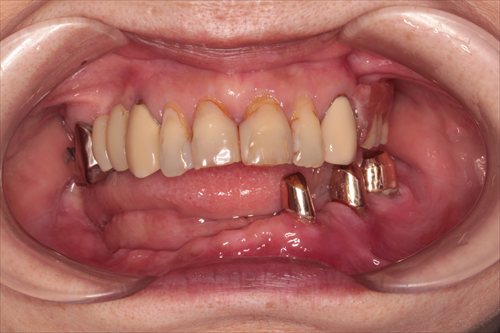

義歯が入ったところです。

義歯を外したところです。歯に内冠と呼ばれるかぶせ物を装着し、その上に義歯をかぶせていきます。